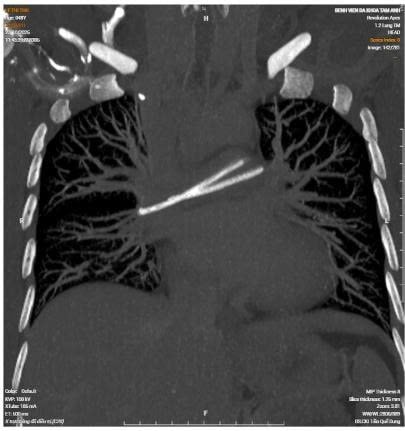

Hình ảnh CT ghi nhận dị vật bên động mạch phổi. Ảnh: BVCC

Trong lần đi khám tầm soát tại một cơ sở y tế tư nhân, người bệnh được chỉ định chụp CT ngực có tiêm thuốc cản quang, bác sĩ phát hiện hình ảnh một dị vật trong tim, nằm vắt ngang tại vị trí động mạch phổi hai bên.

Bác sĩ ghi nhận catheter đã bị đứt, một phần còn tại vị trí dưới xương đòn phải, phần đầu ống truyền còn lại đã di chuyển về tim và nằm trong động mạch phổi. Bệnh nhân được chỉ định rạch lấy phần catheter còn lại dưới da, lấy phần catheter ra ngoài và được đưa đến Bệnh viện Quân y 175 để xử trí chuyên sâu phần trong tim.

ThS.BS Hoàng Hải Anh - khoa Can thiệp Tim mạch, Bệnh viện Quân y 175 cho biết, hầu hết các trường hợp catheter đứt đều dừng lại ở tĩnh mạch ngoại vi, nhĩ phải hoặc thất phải. Đây là lần đầu tiên bệnh viện tiếp nhận dị vật trôi sâu vào tim, và vắt ngang vùng chia hai nhánh động mạch phổi như vậy. Trường hợp này lại đi sâu đến động mạch phổi khiến thao tác xử lý trở nên khó khăn hơn rất nhiều.